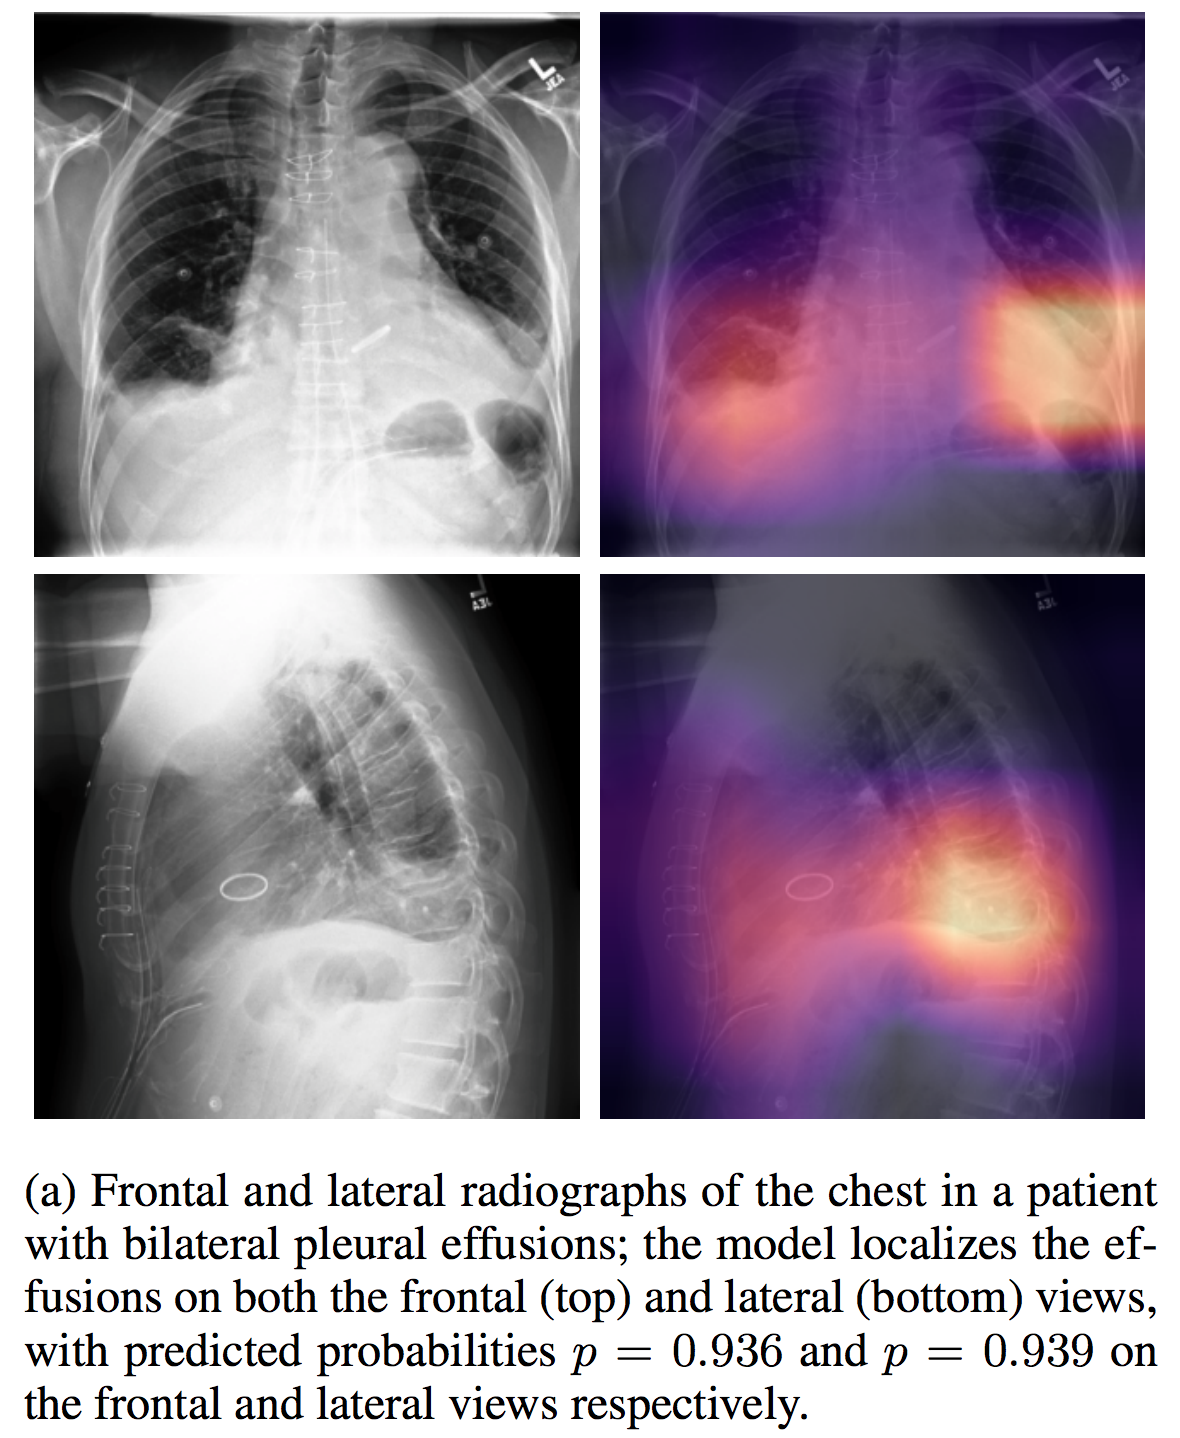

CheXpert

| CheXpert |

介绍论文: CheXpert: A Large Chest Radiograph Dataset with Uncertainty Labels and Expert Comparison